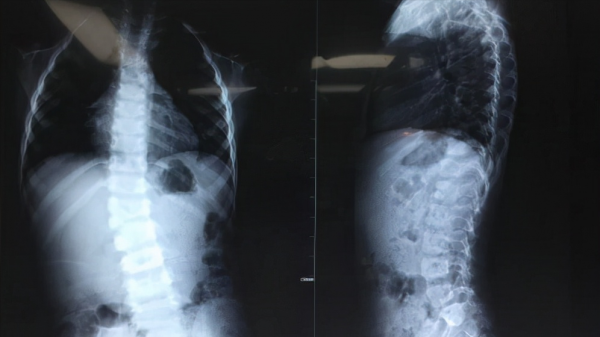

醫院對這類患者通常會製作全長位DR片和CT三維重建,由此可將脊柱很直觀的呈現在眼前。

上圖是一張某一位患者的三維脊柱圖。即便是不懂醫學的普通人,也能一眼看出異常。

圖中脊柱卻有兩處“半椎體消失了”,也就是說,有兩節椎體只有半邊,另一邊沒長出來。

脊柱簡單說就是人體後背的那一條凹凸不平的骨頭,如果孩子的脊柱也有類似的情況,且與圖中一樣嚴重,那麼可以用手撫摸脊柱位,就能明顯察覺到脊柱出現了側彎或者畸形,除此之外,肉眼也可明顯看出孩子出現高低肩、身子歪等情況。